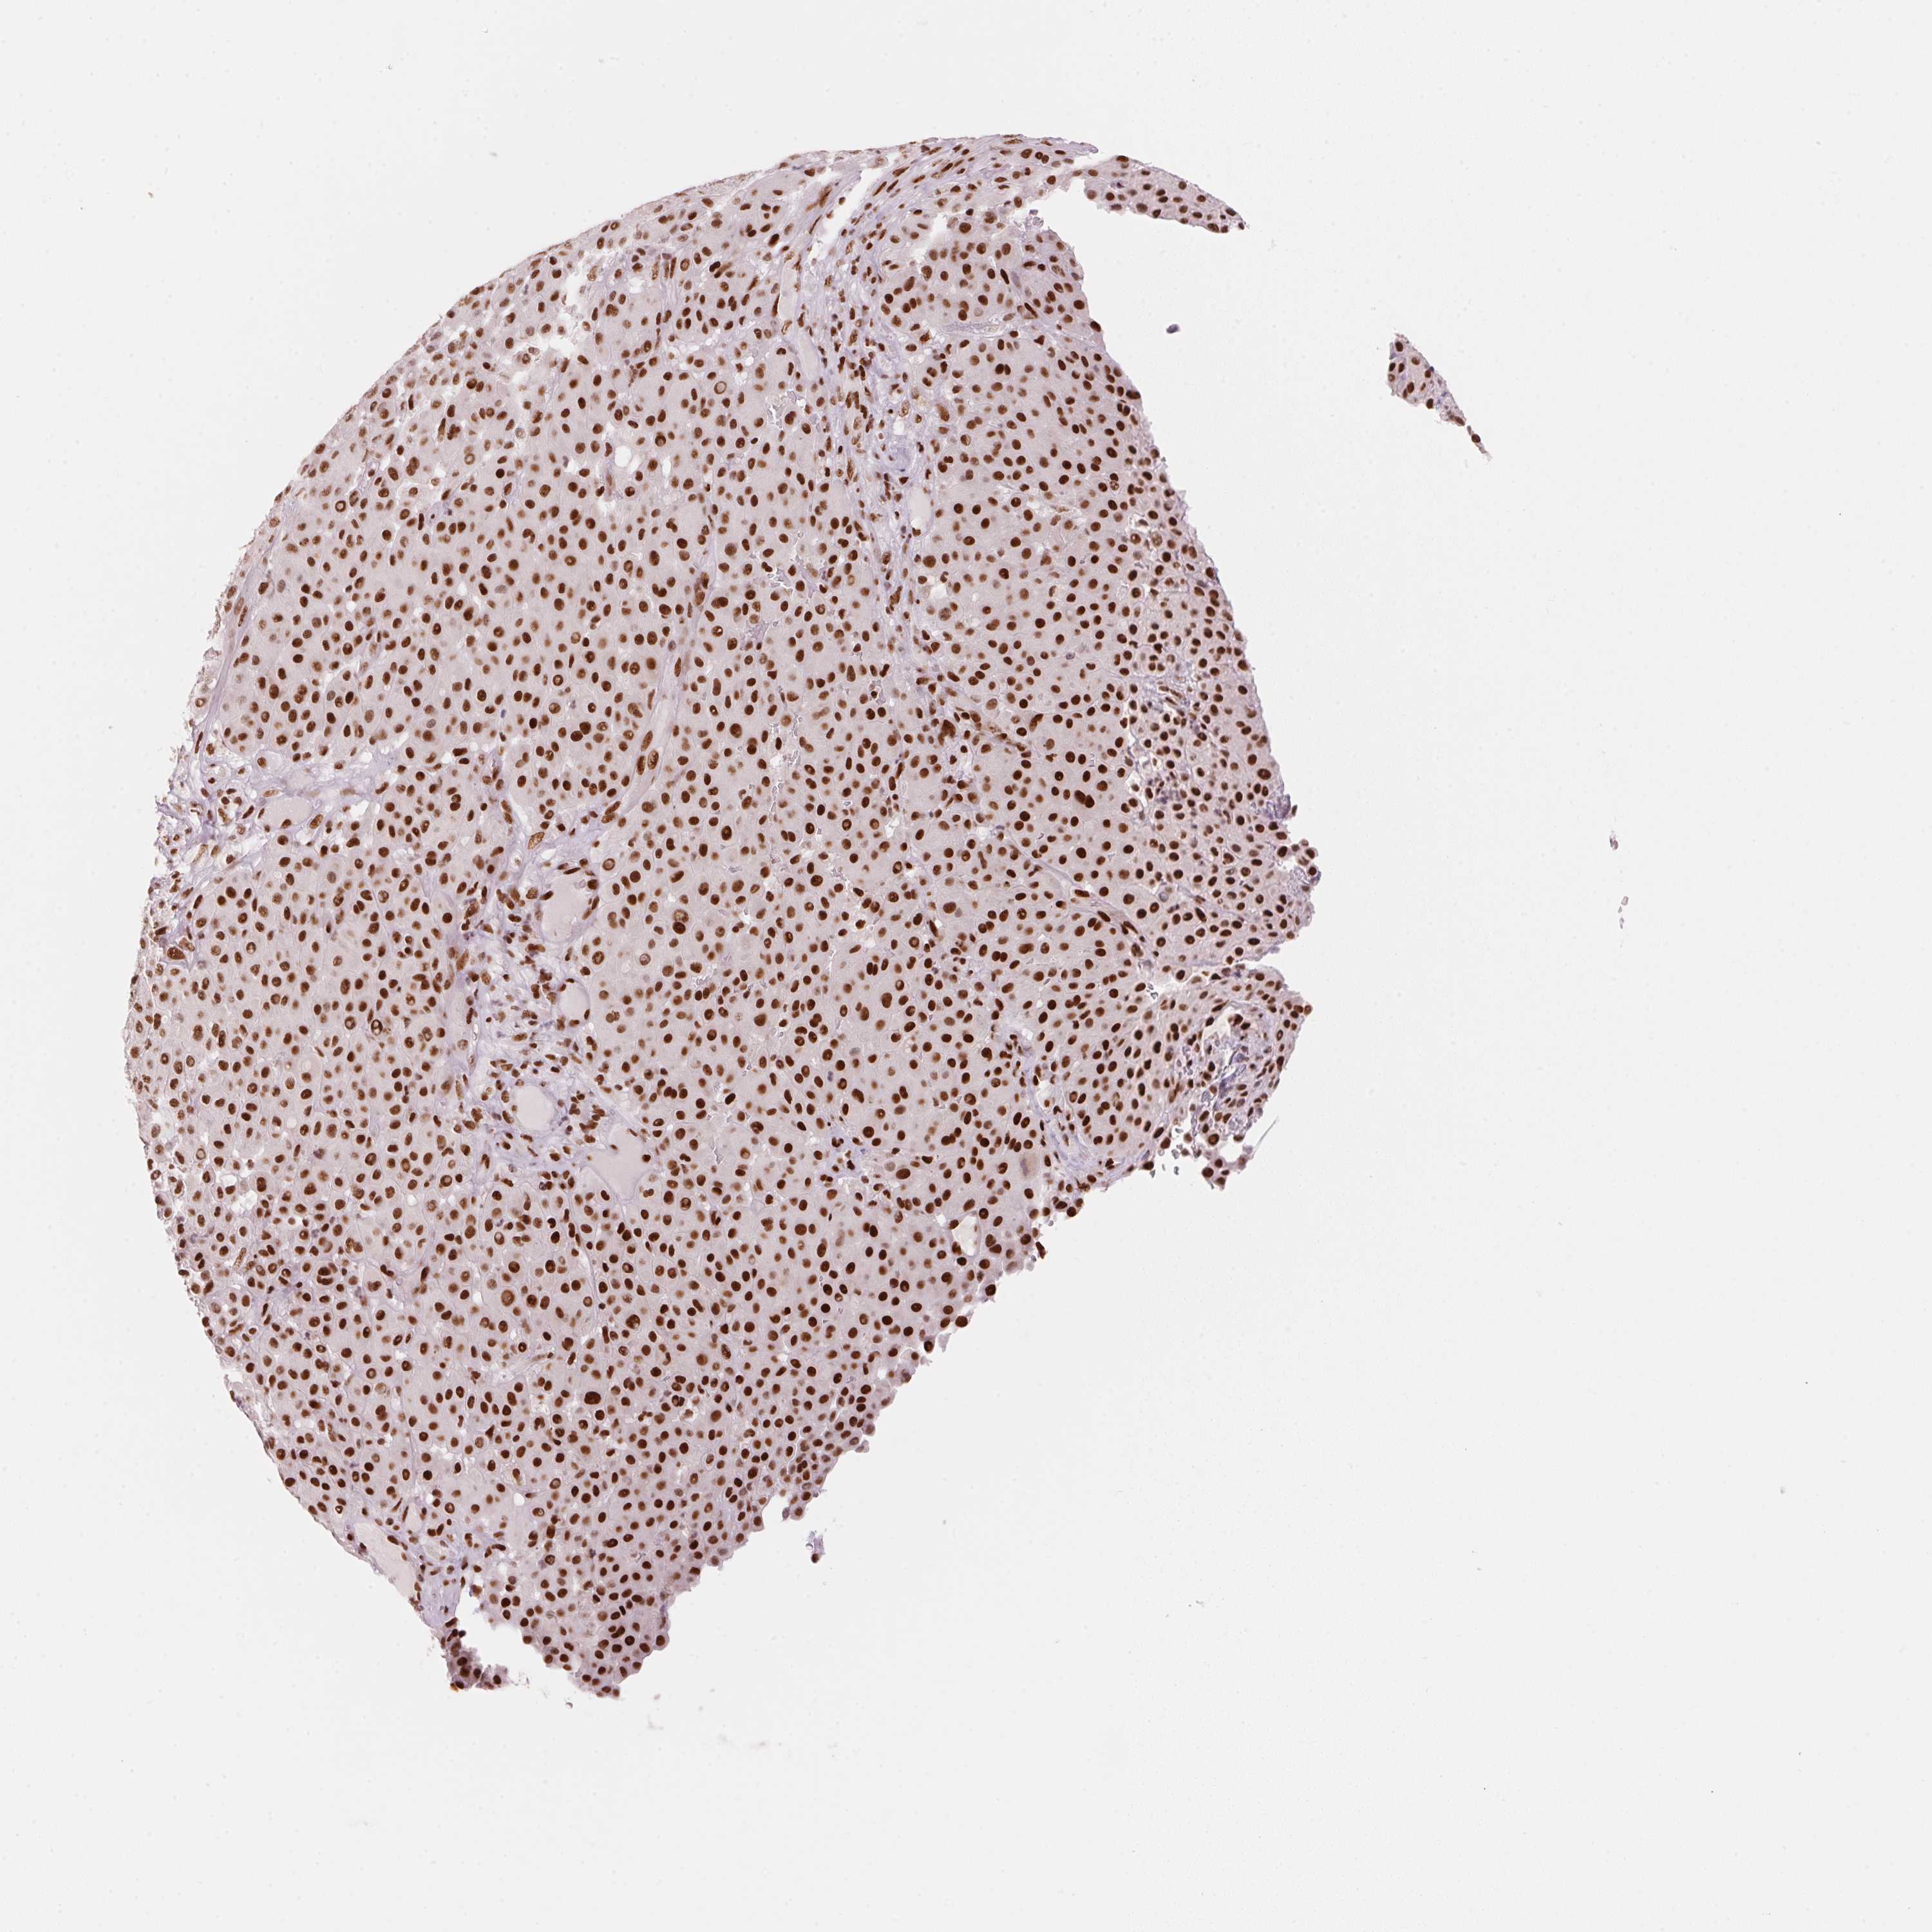

MELANOMA - Protein expressioni

A mouse-over function shows sample information and annotation data. Click on an image to view it in a full screen mode. Samples can be filtered based on level of antibody staining by selecting one or several of the following categories: high, medium, low and not detected. The assay and annotation is described here.

Note that samples used for immunohistochemistry by the Human Protein Atlas do not correspond to samples in the TCGA dataset.

Antibody stainingi

Antibody staining in the annotated cell types in the current human tissue is reported as not detected, low, medium, or high, based on conventional immunohistochemistry profiling in selected tissues. This score is based on the combination of the staining intensity and fraction of stained cells.

Each image is clickable and will lead to virtual microscopy that enables deeper exploration of all samples and also displays staining intensity scores, fraction scores and subcellular localization as well as patient and tissue information for each sample.

Antibody HPA061593

Antibody CAB016327

Staining

High

Medium

Low

Not detected

Intensity

Strong

Moderate

Weak

Negative

Quantity

>75%

75%-25%

<25%

None

Location

Nuclear

Cytoplasmic/membranous

Cytoplasmic/membranous,nuclear

Malignant melanoma, NOS

Malignant melanoma, Metastatic site